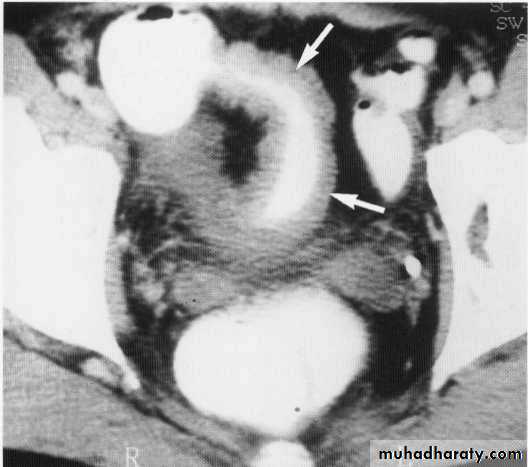

Rectal tumor with local invasion